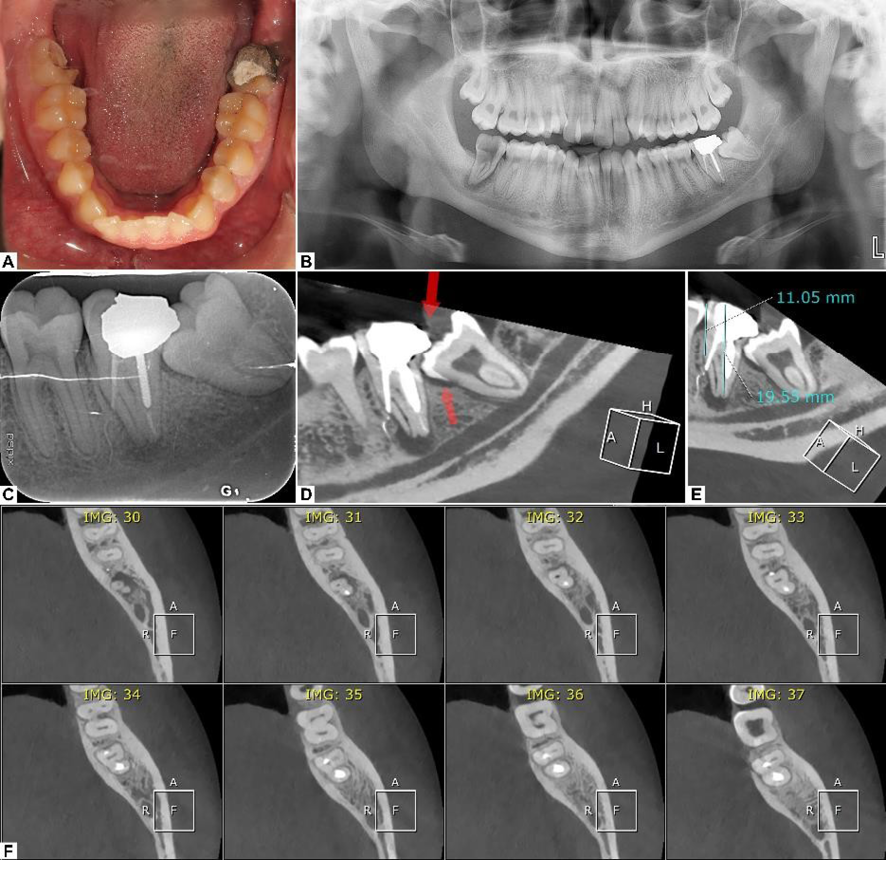

In the examination of the patient’s radiographs, the panoramic and periapical radiographs revealed a suboptimal RCT for the suspected tooth with an apparent lateral perforation of the mesial root. The CBCT radiograph not only confirmed the previous findings but also showed the extent of the periapical lesion and the lateral perforation and that the mesiolingual canal was completely missed in the previous RCT procedure (Figure-1).

Figure 1. (A) Intraoral photograph of the patient’s mandibular dentition. (B) Panoramic radiograph. (C) Periapical radiograph, demonstrating previous suboptimal root canal therapy. (D) CBCT slice depicting extensive periapical lesion. (E) Recipient site measurements. (F) Axial CBCT reconstruction showing lateral root perforation and missed mesiolingual canal in the second molar.